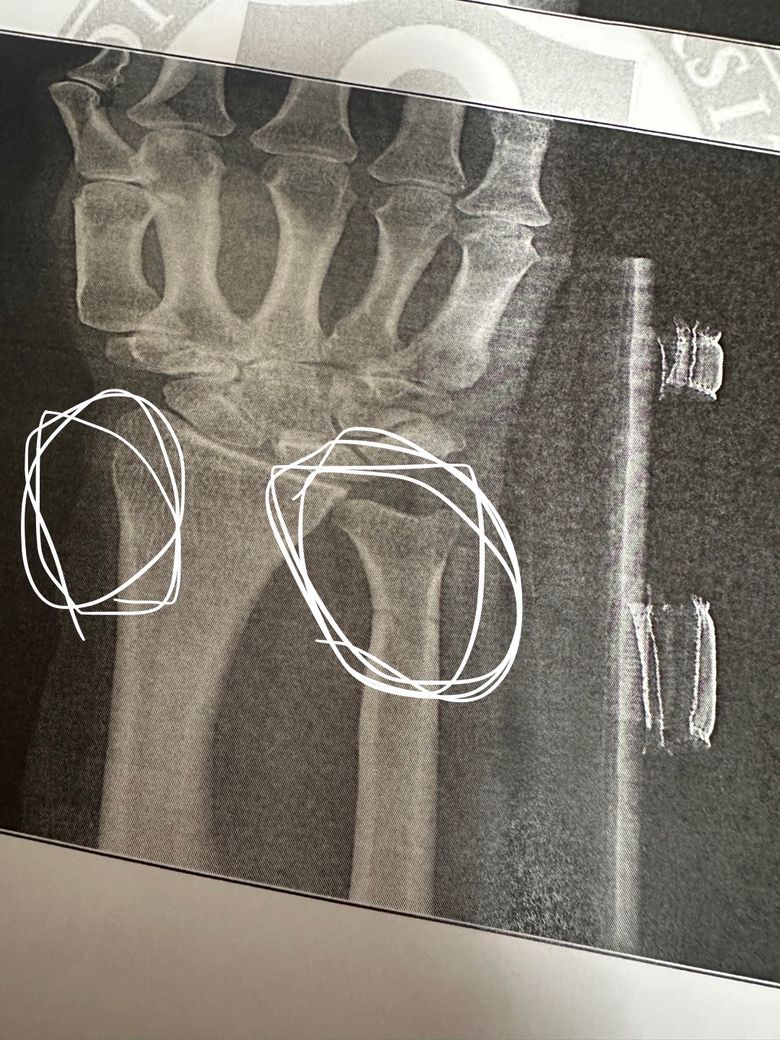

손목 뼈 흰색 선 테두리, 손목 실금 유무

뼈 테두리에는 흰색 선이 있는데, 제 손목 x-ray 보면 잘 안 보인다고 하시면서 실금간 걸 수도 있다고 하시는데, 정말 선이 잘 안 보일까요

아무래도 뼈와 같은 밀도가 높은 조직은 하얗게 표시가되지만 실금 또는 골절이라면 하얗게 표시되는 부분이 잘 안보일 수 있습니다.

엑스레이에서 실금은 뼈 테두리의 연속된 흰 선이 끊기거나 흐려지는 모습으로 보이는데 초기에는 정말 잘 안 보이는 경우가 많습니다. 특히 손목처럼 작은 뼈가 겹쳐 보이는 부위는 골절 선이 희미하거나 가려질 수 있습니다.의심 소견이 있으면 보통 1~2주 뒤 재촬영하거나 ct, mri 같은 정밀검사를 권유하기도 합니다. 따라서 통증이 지속된다면 추가 검사 또는 고정치료를 받는 것이 안전합니다!